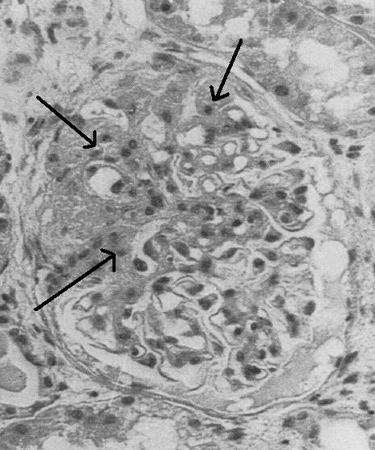

Glomeruloesclerosis focal y segmentaria

Microscopía óptica de biopsia renal que muestra lesiones típicas de la glomeruloesclerosis focal y segmentaria

Adaptado de Nagi AH, Alexander F, Lannigan R. Light and electron microscopical studies of focal glomerular sclerosis. J Clin Pathol. 1971 Dec;24(9):846-50